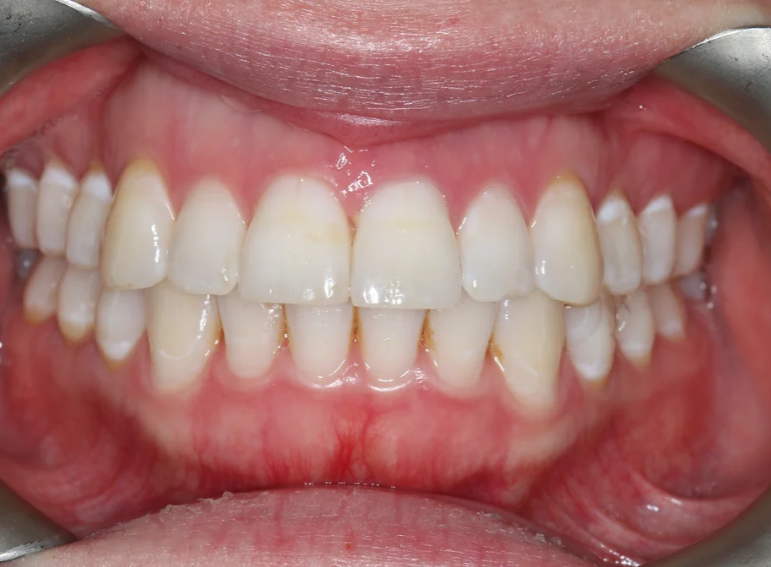

Root canal treatment and combined internal and external whitening.